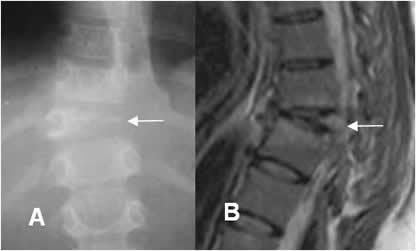

Fig 24. Malformación asociada.

A: Rx AP. Escoliosis dorsolumbar izquierda.

B: RM sagital en T2. Descenso de las amígdalas cerebelosas a través del agujero magno, por malformación de Chiari I (Flecha) y cavidad de siringomelia en la columna cervical. Fotos tomadas de la referencia 24.